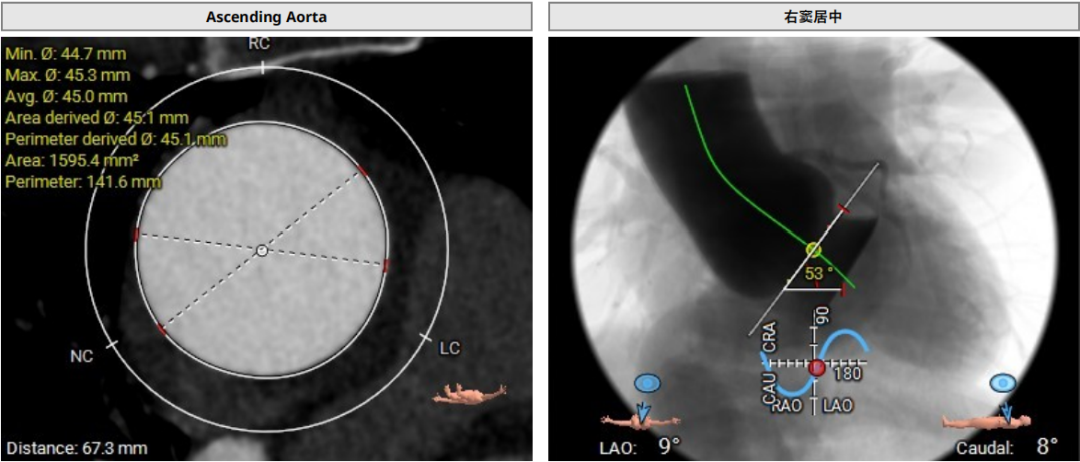

术前CT评估示

三叶瓣,瓣环面积约578.0mm²,折算瓣环直径27.1mm,LVOT约618.8mm²,折算直径28.1mm,SOV:46.1*42.9*43.4mm,窦部空间较大,瓣叶长度适中,瓣叶明显增厚,STJ:32.3(H)* 43.1mm (D),STJ直径和高度足够;LCA:22.6mm,RCA:22.9mm,瓣叶长度适中,窦部空间足够;瓣环夹角53°。

模拟29mm瓣膜植入情况:

血管入路评估:血管穿刺位点直径可,腹主动脉-降主动脉段接近90°迂曲。

78岁男性患者,主动脉瓣重度反流,瓣环面积约578.0mm²,折算瓣环直径27.1mm,LVOT约618.8mn折算直径28.1mm,轻度横位心,腹主动脉-降主动脉段迂曲,同时合并心功能不全,肺癌手术,属于外手术风险高危患者。经手术团队综合评估,患者为纯反流病例,瓣叶增厚并不明显且LOVT面积更大,仅瓣叶交界有少量钙化,对瓣膜锚定径向支撑力的要求很高,经过团队反复讨论,实施模拟分析后,拟行经导管TAVR术,拟以右侧股动脉为主入路,拟入29#SAPIEN3瓣膜,术中拟+3cc释放来实现oversize22%,于80/20位置释放,通过瓣环和瓣交接钙化实现瓣膜锚定,视情况选择是否后扩。